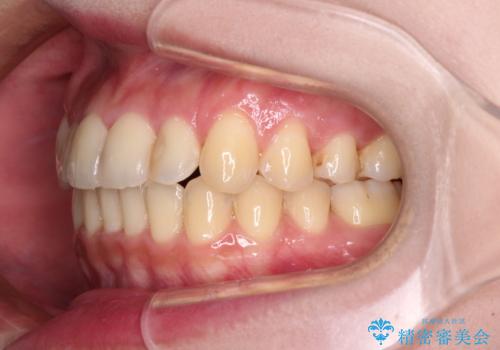

- 前歯のデコボコを気にして来院された患者様です。

上顎右側犬歯が八重歯になっており、それによって奥歯が前方に移動しているため、右側の咬み合わせの改善が必要と判断されました。

マウスピース矯正では改善に時間がかかる、あるいは改善しきれない可能性があることを伝えたところ、短期間で確実に治療ができるワイヤー矯正を選択されました。